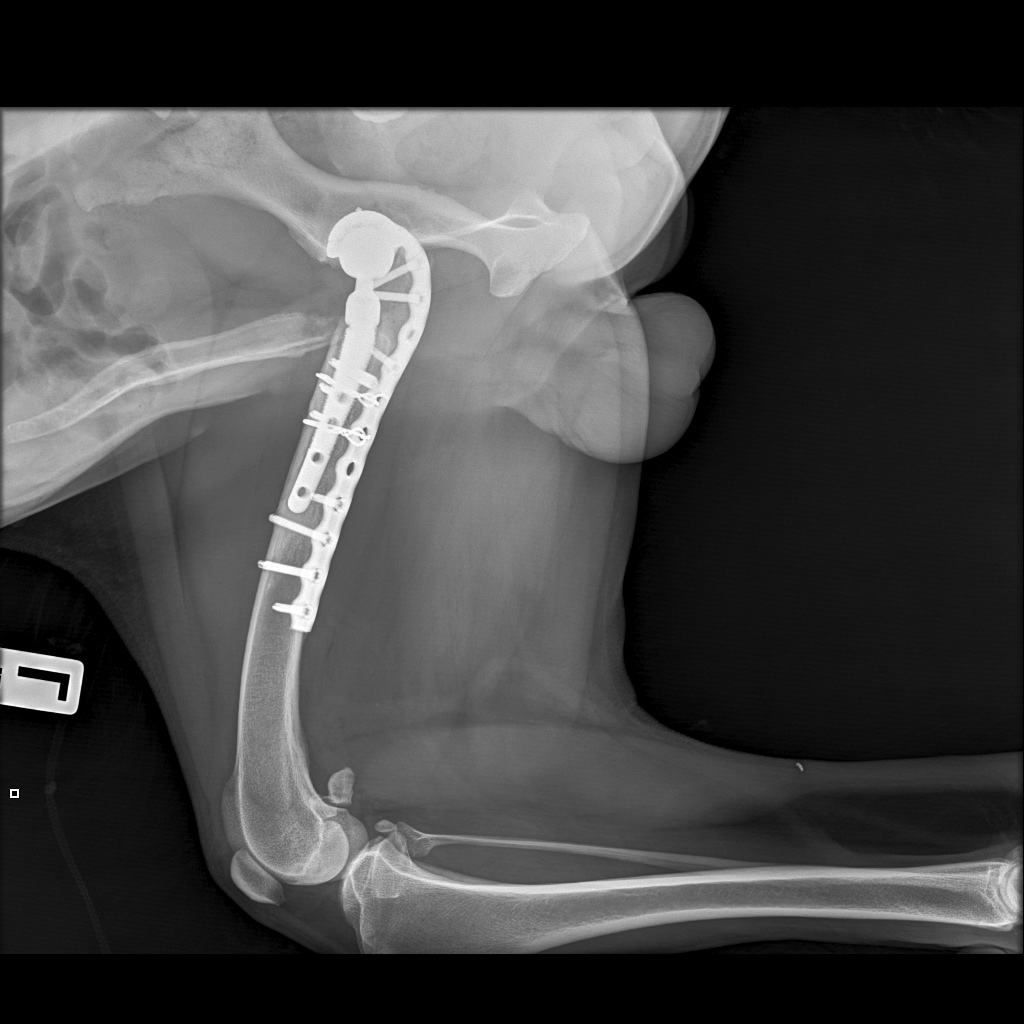

Вчера резко захромал, встал на 3 ноги и понос.

По рентгену чисто